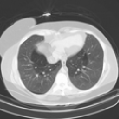

IV-F1 GeMix leads to more realistic images

One of our hypotheses is that GeMix is supposed to lead to more realistic images than traditional mixup or MMixup. Figure 2 illustrates a few examples produced by mixup (first column), MMixup (second column) and GeMix (third column). We observe that GeMix produces more anatomically coherent images, whereas the interpolation in pixel-space performed by mixup and MMixup leads to images that are not anatomically valid.